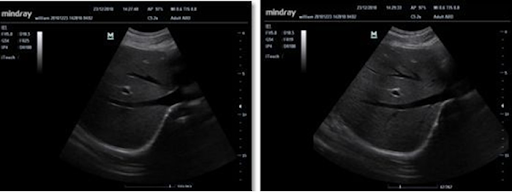

Портативная переносная система цветной допплерографии УЗИ-сканер Mindray M7 отличается самой высокой функциональностью. УЗ-сканер M7 оснащен специальным пакетом опций для кардиологических обследований и программным обеспечением для организации рабочего процесса. УЗИ-сканер Mindray M7 предполагает возможность 4D визуализации, отличается малыми размерами, что позволяет ему легко размешаться в небольших кабинетах и малогабаритных помещениях.

Оснащенная мобильной тележкой, обладающая качеством визуализации и функционалом сопоставимыми со стационарными ультразвуковыми сканерами, система M7 объединяет в себе мобильность, эффективность и высокую производительность. Другими словами, портативная система М7 позволит Вам проводить исследования также эффективно, как на стационарных ультразвуковых аппаратах.